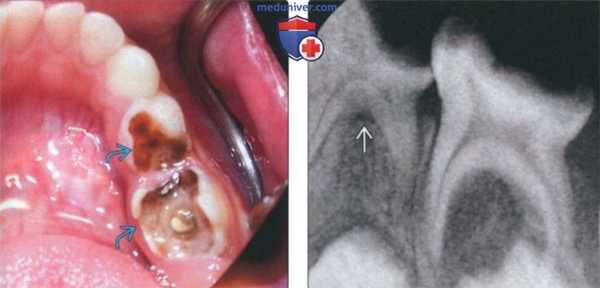

(Слева) На фотографии виден глубокий кариес первого и второго временных моляров.

(Справа) На периапикальной рентгенограмме у этого же пациента определяется расширение области фуркации «мертвого» временного моляра. Рарефицирующий остеит временных моляров возникает в области фуркации вследствие минимального расстояния между пульповой камерой и костной тканью возле фуркации.